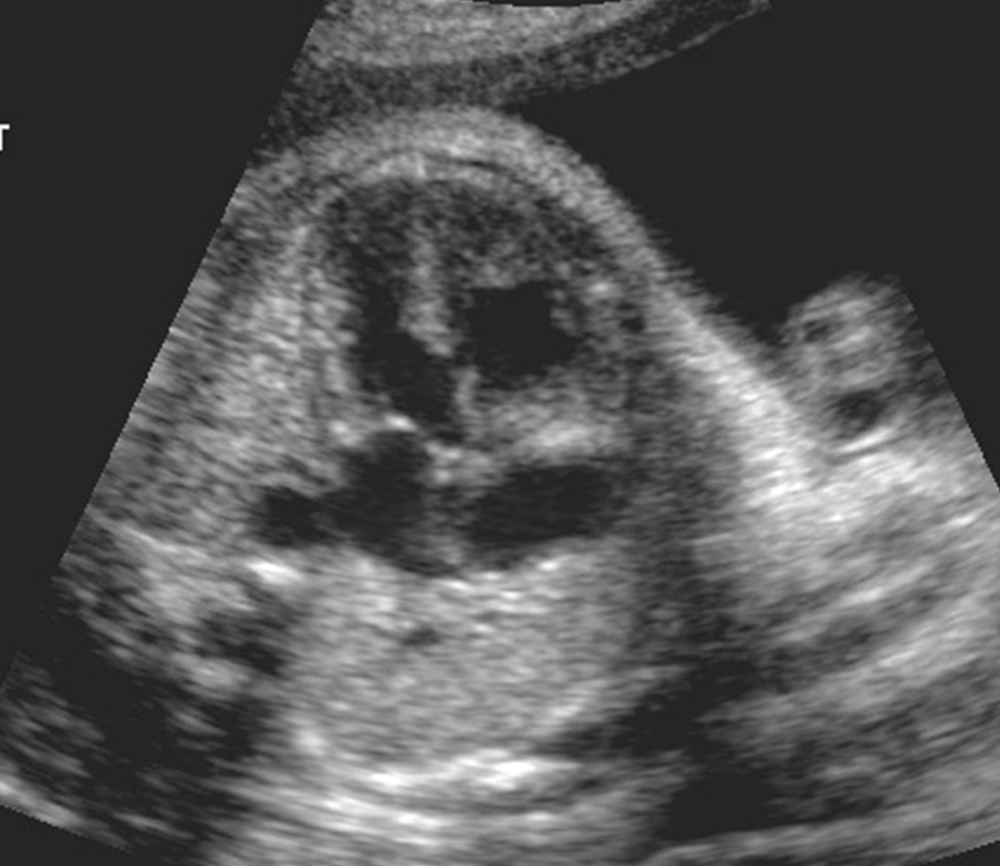

What view is this?

4 chamber view

Normal 4 chamber view

Identify structures of the heart